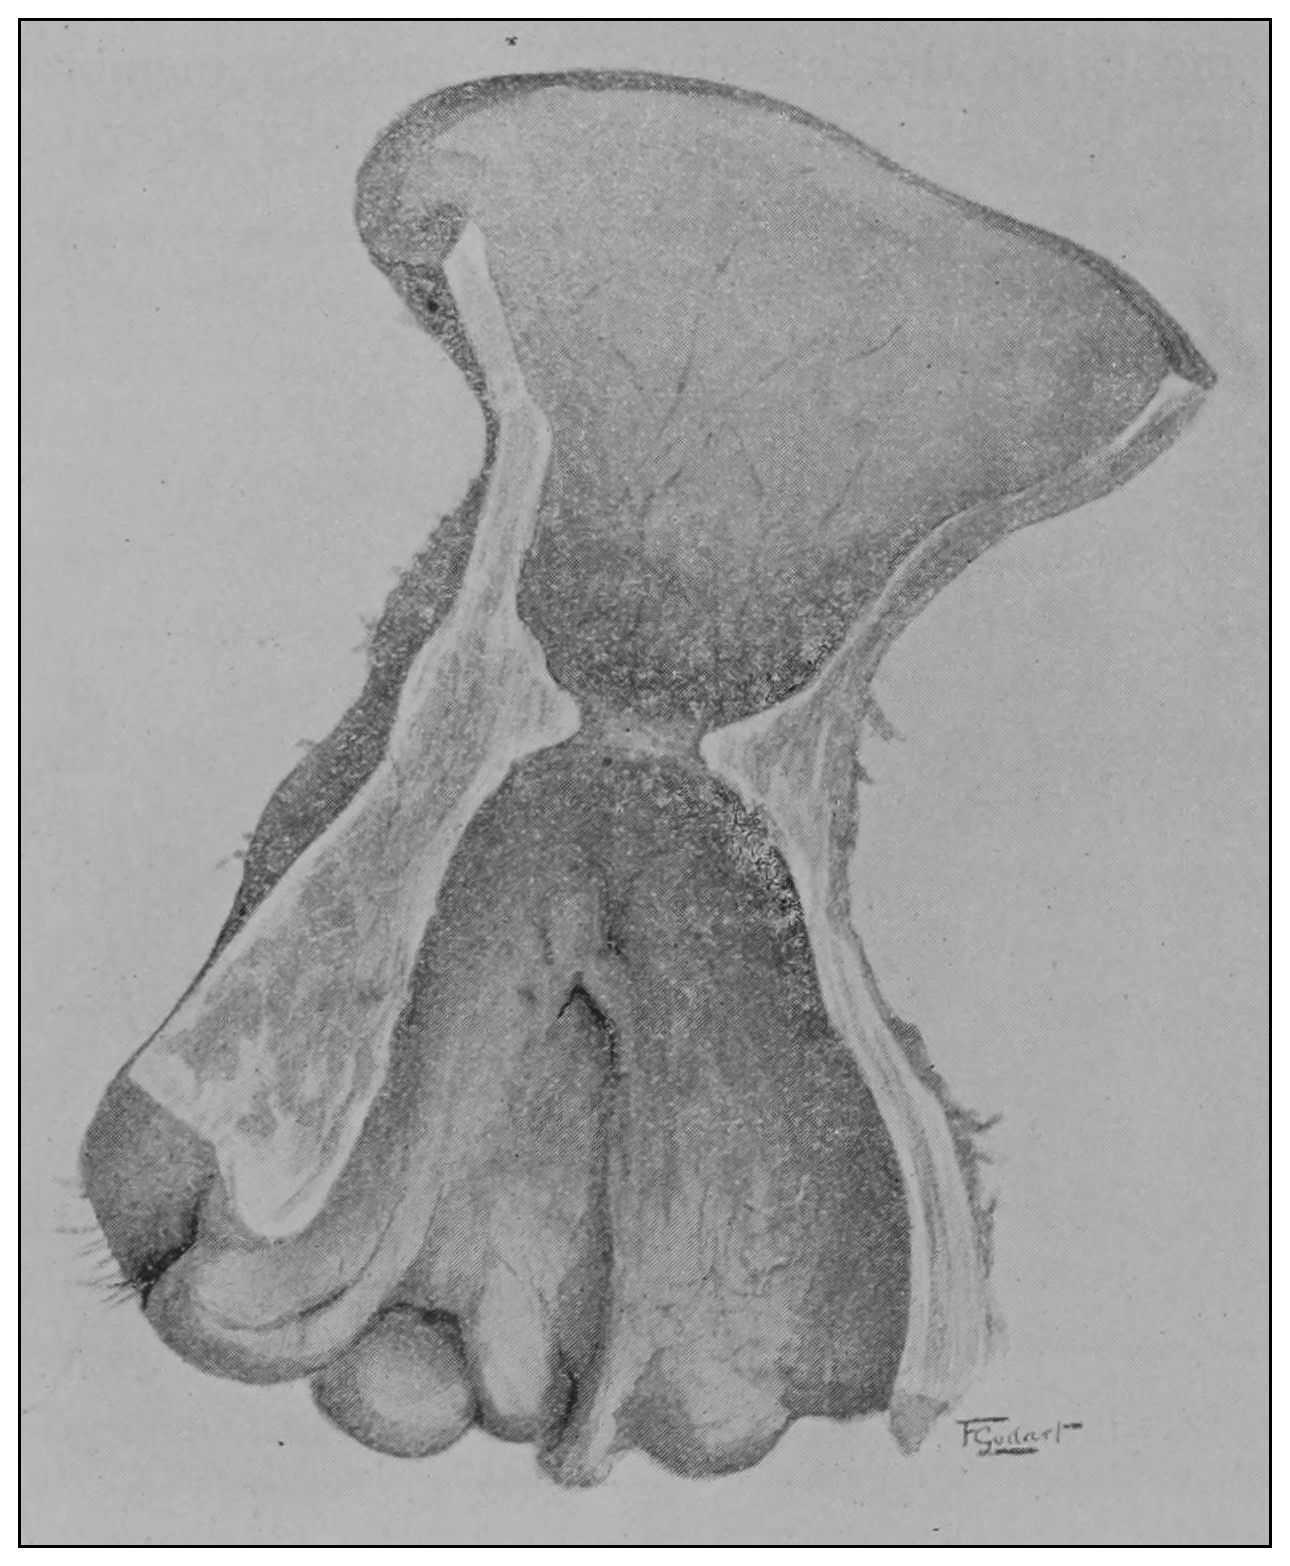

Fig. 19.—Drawing of specimen No. 281 in the Anatomical Museum of the Royal College of Surgeons, London. The dissection was made by Mr. William Pearson. The drawing shows in the lower part of the field the coccyx, in the upper part of the field the pubes.

Fig. 20.—Drawing of specimen No. 284 in the Anatomical Museum of the Royal College of Surgeons, London. The dissection was made by Mr. William Pearson. The drawing shows in the lower part of the field behind the rectum the coccyx, in the upper part of the field the pubes.